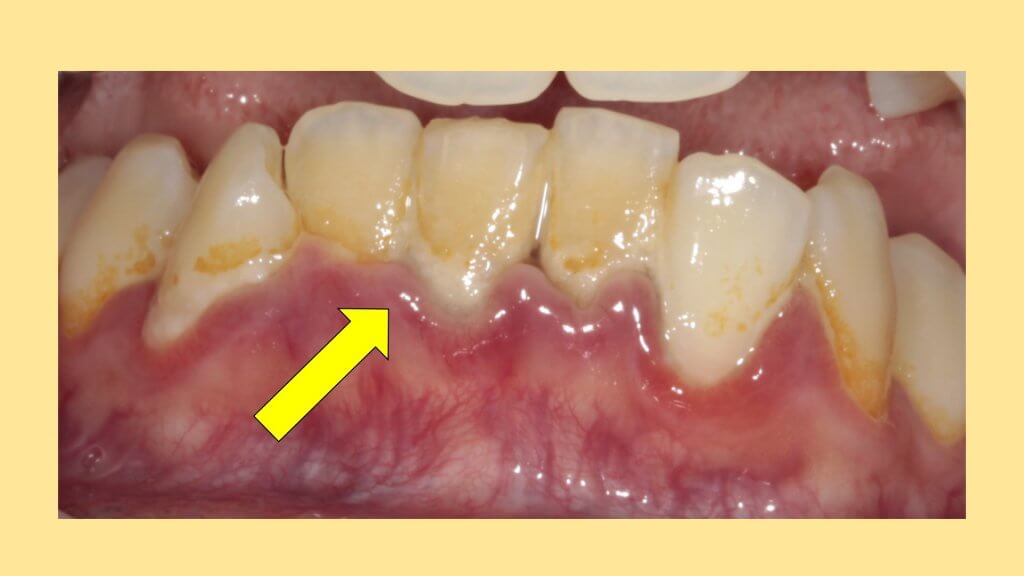

歯周病によるもの

歯ぐきが腫れる代表的な病気です。歯周病は歯肉炎と歯周炎に分けられますが、プラークや歯石、バイオフィルムが付着することで歯肉や歯槽骨で炎症が起きその結果として歯ぐきが腫れます。